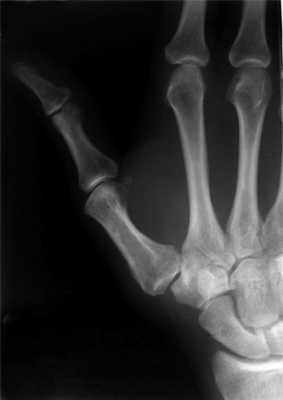

Перелом основания I пястной кости. Характерная травма для боксеров и бойцов MMA. Различают перелом Беннета — отрыв участка основания первой пястной кости, который удерживается связками, с одновременным вывихом ее большей части в запястно-пястном суставе. Перелом Роландо — многооскольчатый переломовывих I пястной кости. Обе травмы проявляются болью, деформацией и отечностью в области “анатомической табакерки” — области под основанием первого пальца — с усилением боли при движении, попытке сжать кулак. Диагностика осуществляется с учетом жалоб, данных анамнеза травмы, осмотра области повреждения и рентгенографии кисти. Лечат переломы Беннета и Роландо хирургическим путем с применением остеосинтеза — восстановления целостности кости путем фиксации отломков металлическими спицами, штифтами или пластинами.

Перелом средней части I пястной кости. Чаще возникает вследствие прямого удара по кости. Проявляется болью, отеком и деформацией в области первой пястной кости. Диагноз устанавливается с учетом жалоб пациента, сведений о механизме повреждения, осмотра области первой пястной кости и рентгенологического исследования костей кисти. Лечение — гипсовая иммобилизация сроком 4-5 недель, при смещении отломков — предварительная закрытая репозиция. При неэффективности консервативной репозиции для сопоставления отломков проводится операция — спицевой остеосинтез.

Пример операции доктора Валеева по восстановлению после перелома первой пястной кости:

Причина — удар кулаком или падение на сжатые в кулак пальцы. Могут быть одиночными, но чаще ломаются несколько пястных костей, обычно — четвертая и пятая. Проявляется болью, отеком и деформацией кисти, нередко возникает гематома. Диагностируется на основании жалоб, анамнеза травмы, объективного осмотра и результатов рентгенографии костей кисти. Для лечения перелома без смещения выполняется иммобилизация сроком на 4-5 недель. При смещении отломков показана закрытая репозиция, а при ее неэффективности — скелетное вытяжение или спицевой остеосинтез.